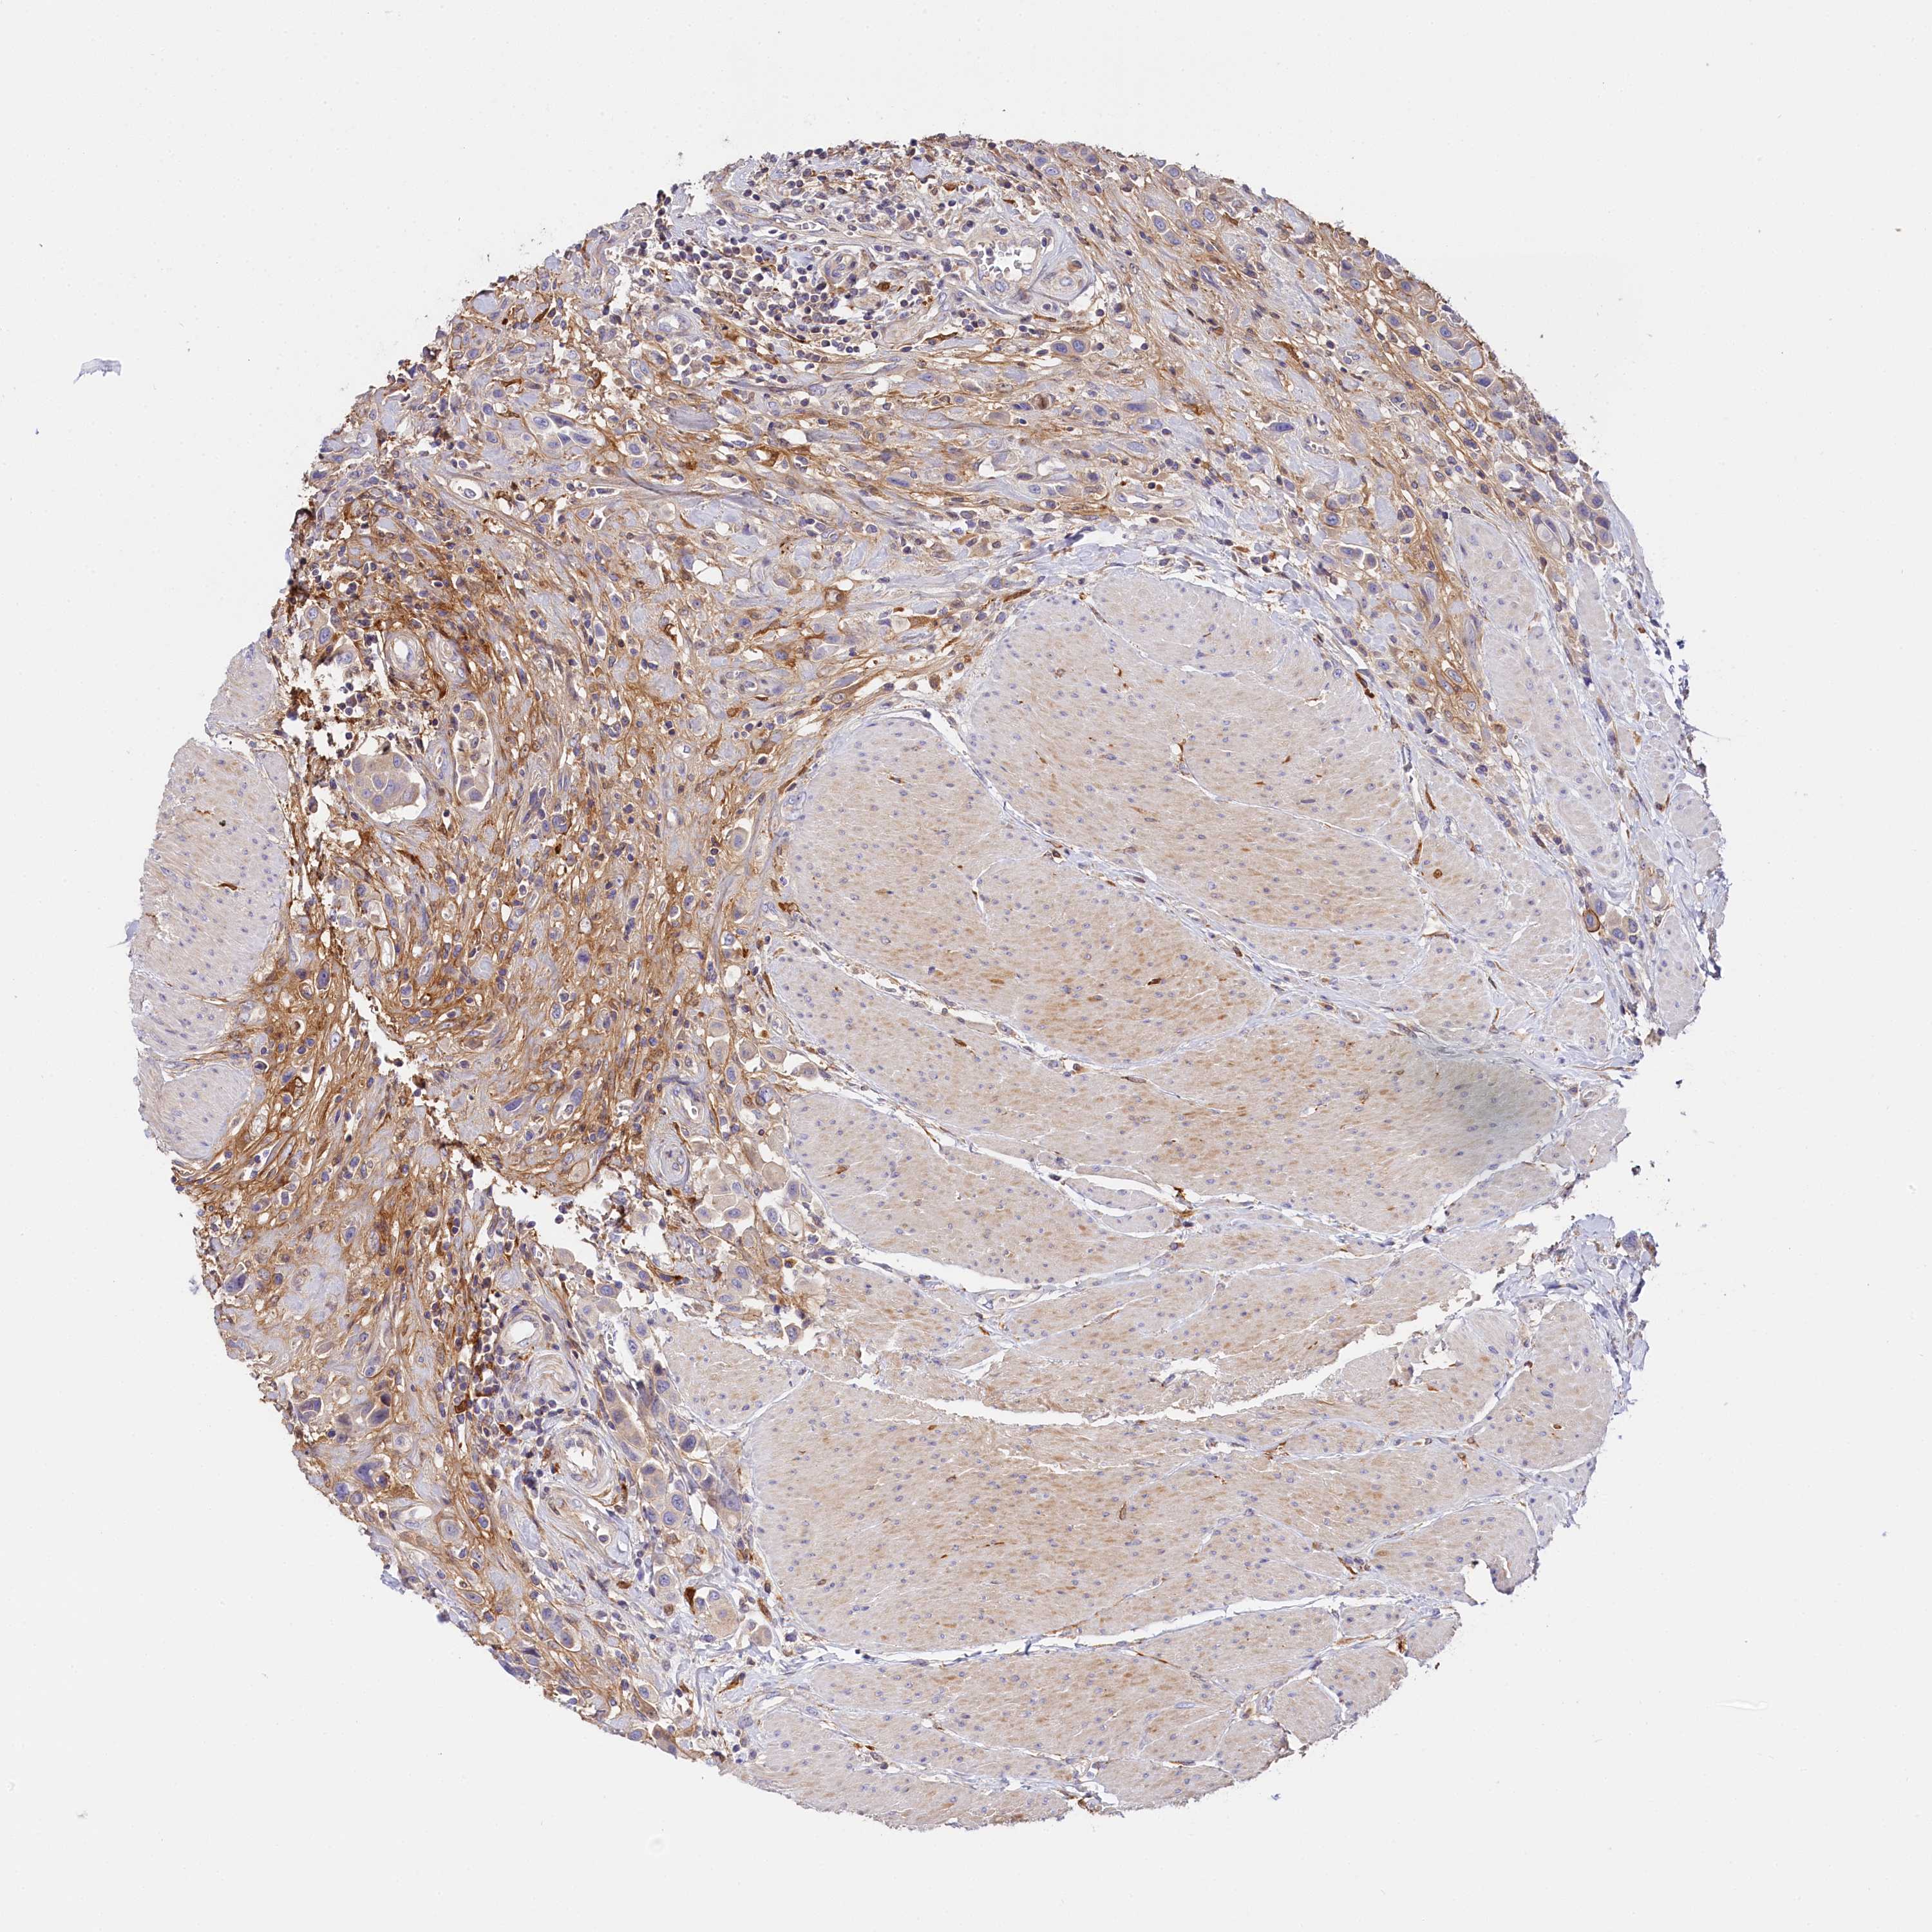

UROTHELIAL CANCER - Protein expressioni

A mouse-over function shows sample information and annotation data. Click on an image to view it in a full screen mode. Samples can be filtered based on level of antibody staining by selecting one or several of the following categories: high, medium, low and not detected. The assay and annotation is described here.

Note that samples used for immunohistochemistry by the Human Protein Atlas do not correspond to samples in the TCGA dataset.

Antibody stainingi

Antibody staining in the annotated cell types in the current human tissue is reported as not detected, low, medium, or high, based on conventional immunohistochemistry profiling in selected tissues. This score is based on the combination of the staining intensity and fraction of stained cells.

Each image is clickable and will lead to virtual microscopy that enables deeper exploration of all samples and also displays staining intensity scores, fraction scores and subcellular localization as well as patient and tissue information for each sample.

Antibody HPA041165

Antibody HPA041839

Urothelial carcinoma, High grade

Urothelial carcinoma, Low grade